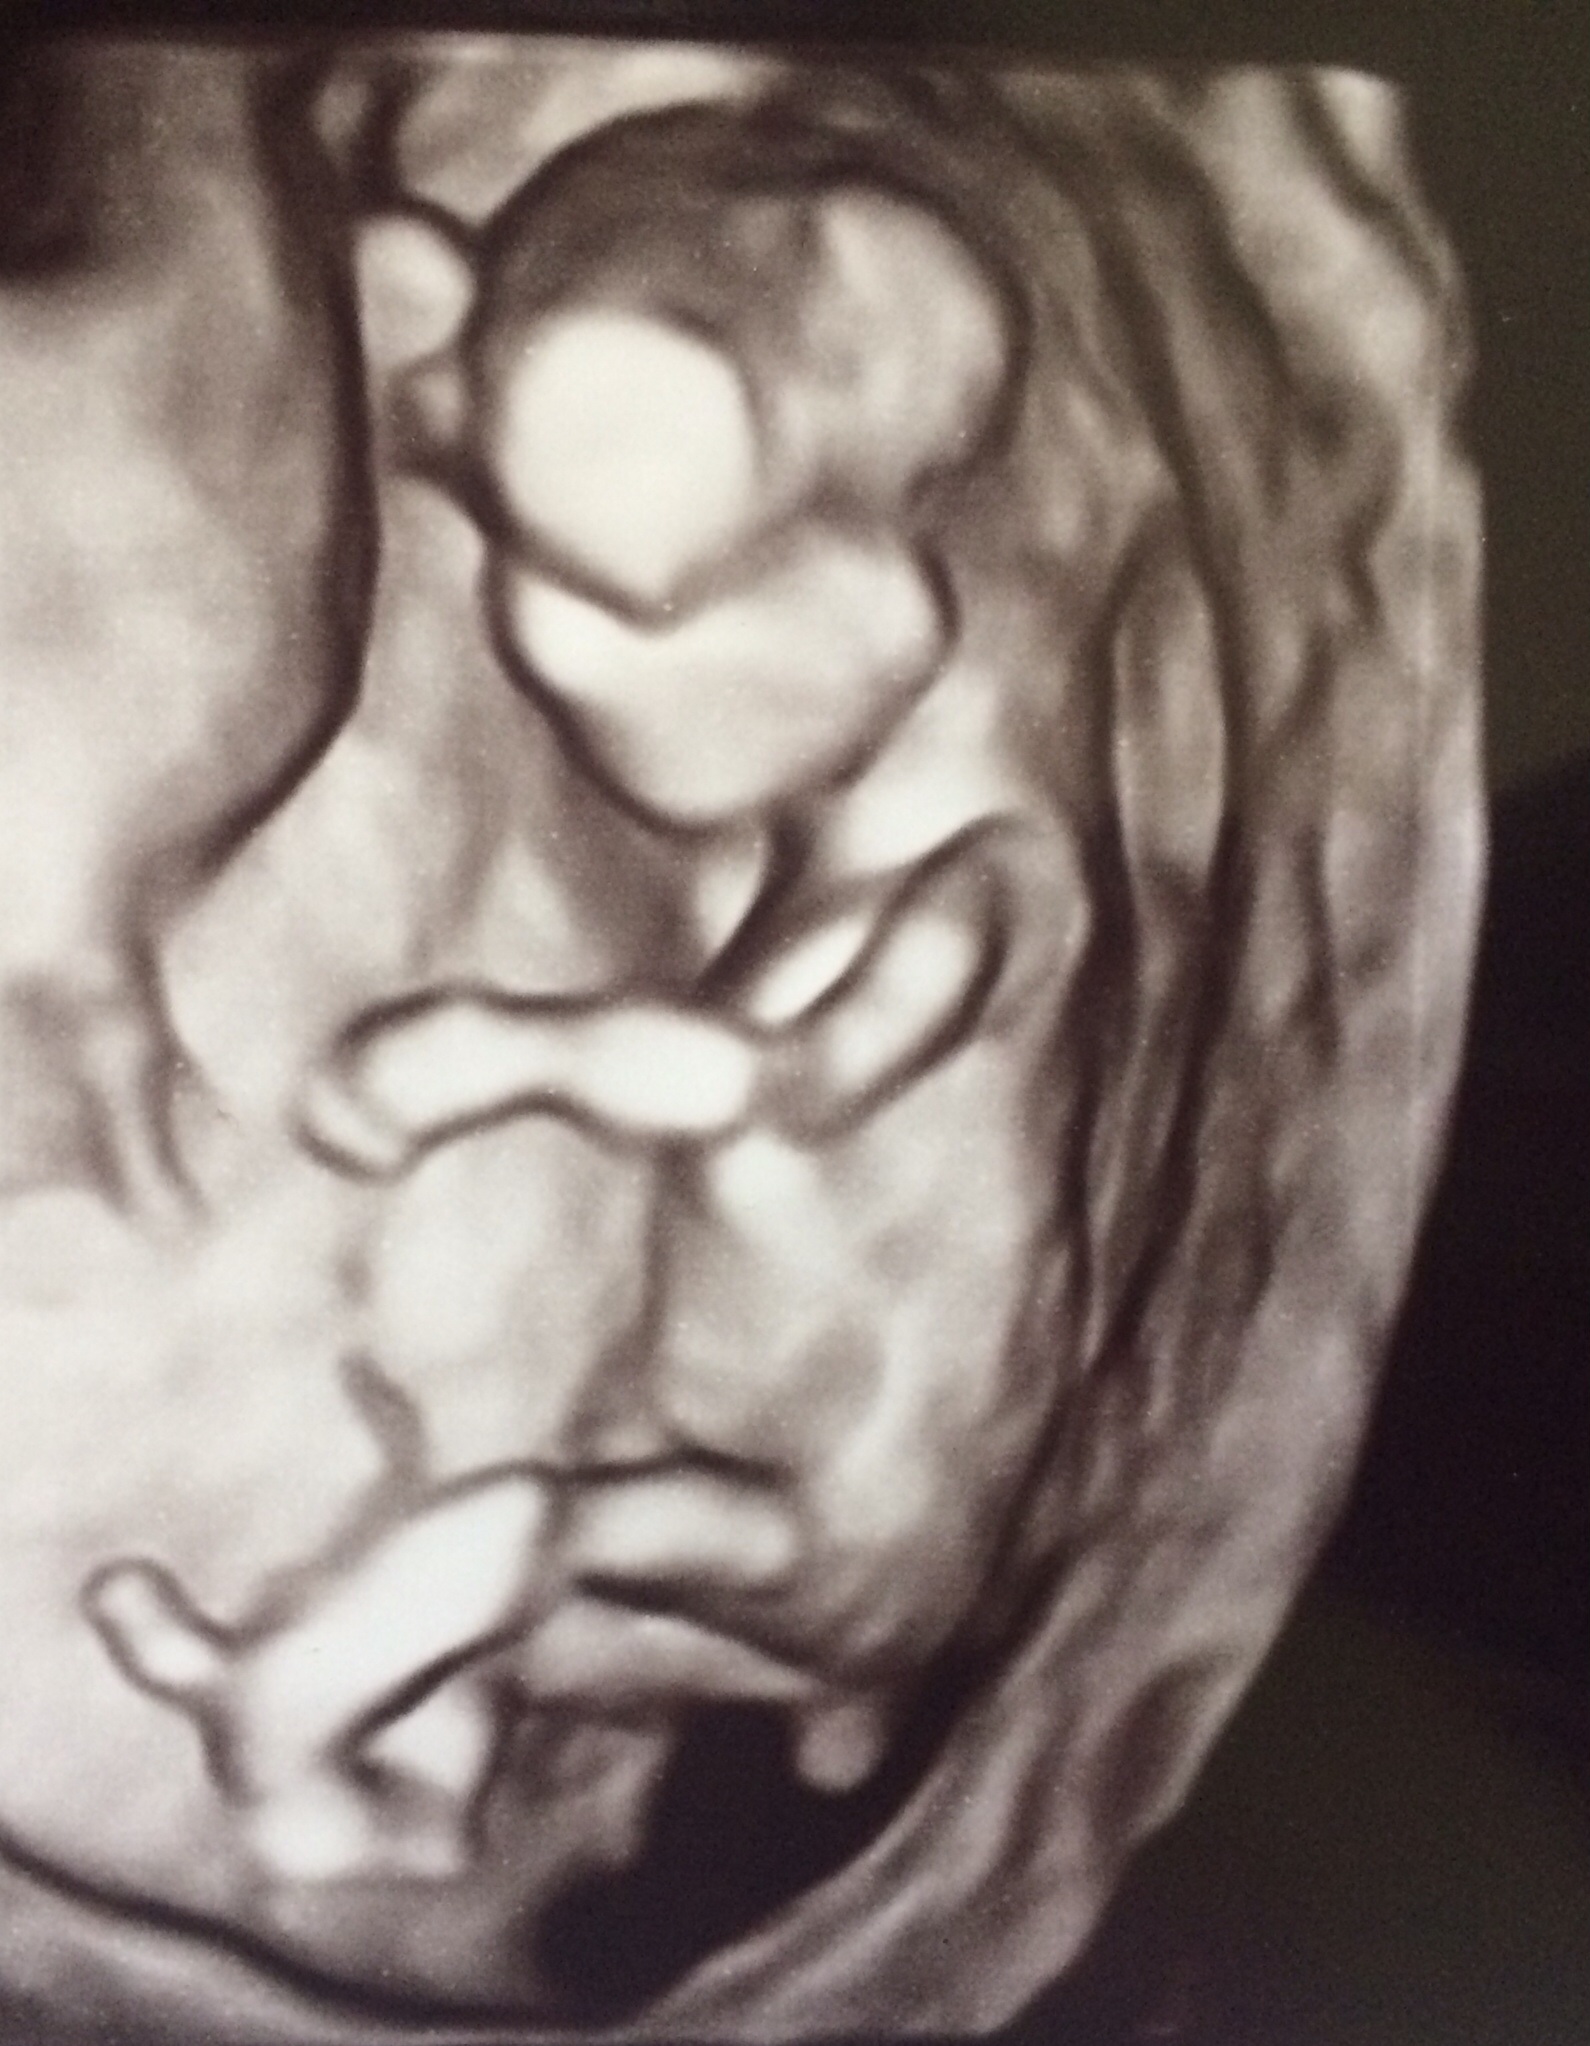

4D 12 weeks, 5 days

Guesses welcome! Will update when I find out!

Maybe boy from last picture? But none are very clear of nub.

Thinking boy from last picture. Congrats! x

Boy guess here as well